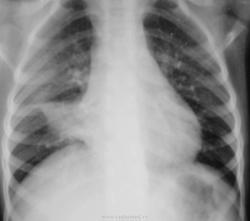

Девочка 5 лет.Проходила обследование для консультации пульмонологом респуб.больницы как часто болеющая.Жалоб особо нет,редкое покашливание.Температура нормал.,хрипов в легких нет.ВАШЕ МНЕНИЕ?

Междолевой осумкованный выпот.

На мой взгляд - ателектаз средней доли правого легкого. Показана бронхоскопия.

Ателектаз средней доли справа. Рекомендована бронхоскопия.

На мой взгляд, картина типичная для среднедолевого синдрома

По моему обтурационный ателектаз средней доли. Обследовать на предмет инородного тела.

А почему ателектаз? Нормальный размер гомогеннозатемненного S5. Только где он на боковой? На боковой похоже на м/д плеврит. Может все-таки осумкованный медиастинальномеждолевой плеврит?

Ателектаз сохраняется, просто контуры его на этой рентгенограмме выглядят нечеткими (немного другое положение ребенка, для лучшей визуализации ателектаза средней доли лучше положение гиперлордоза, как в первом случае).

1. Интересный "ателектаз" средней доли без смещения средостения...

2. Интересный "ателектаз" средней доли веретенообразной формы

3. А, то не известковые включения в правом корне?

Смещения срединной тени может и не быть, постоянно вижу ателектазы средней доли у детей, смещения средостения нет. Веретенообразня форма тени ателектаза на рентгенограмме в боковой проекции тоже характерна для ателектаза средней доли. Читаем еще раз

Созванивалась с мамой ребенка.Бронхоскопию не делали,только рентген.Со слов мамы: на снимках лучше,диагноз:пневмония